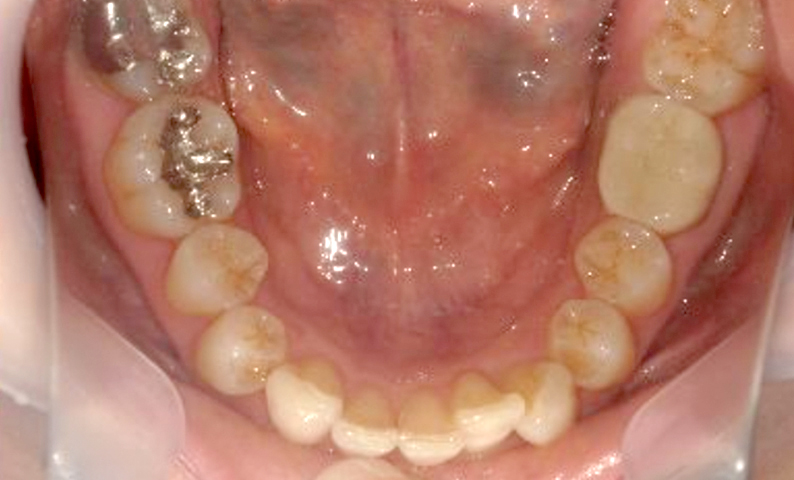

症例_001 下顎だけの部分矯正

治療期間:8ヶ月金額:21万円+税女性前歯のガタガタ下の前歯だけ

| Before | After |